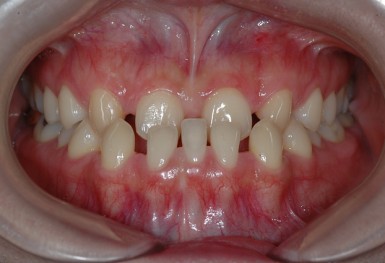

심한 덧니